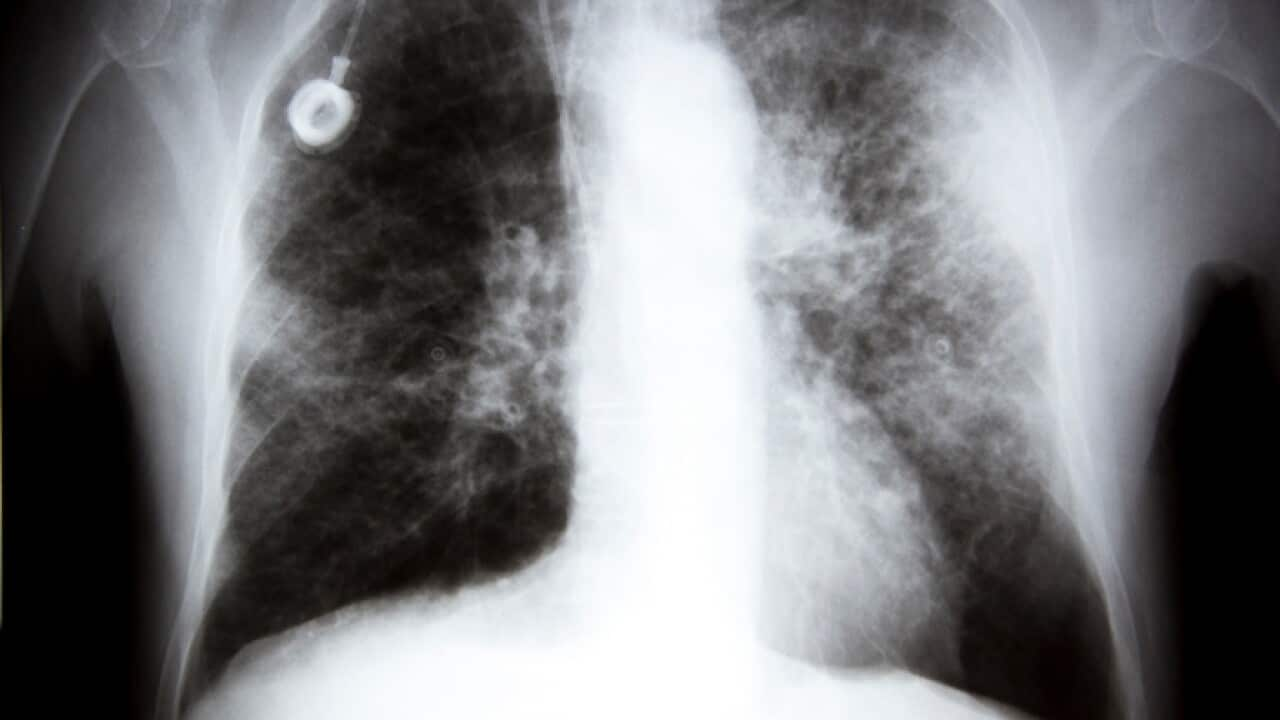

Ngunit ngayon na ang sakit ay kinilala bilang pinaka-nakamamatay na uri ng cancer sa Australya, hinihikayat ng mga eksperto ang muling pag-iisip ng mga paraan upang mabatid nang maaga ang sakit.

Mga dalubhasa hinikayat na pag-isipang muli ang iskrining sa lung cancer

Ang mga screening sa kanser sa baga ay matagal nang nakikitang mahal at minsan ay hindi maaasahan.